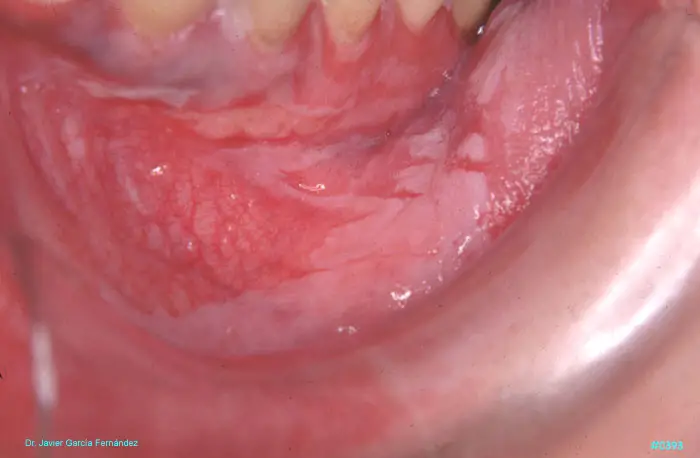

ATLAS DE CIRUGIA PERIODONTAL

image392